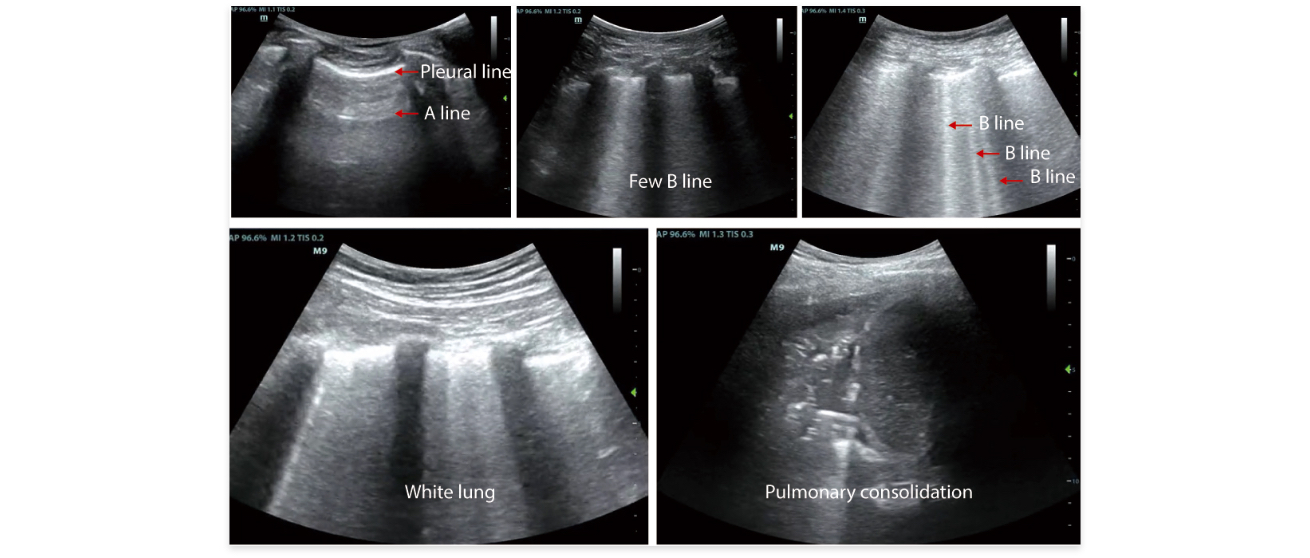

- 1. Professional lung examination mode to observe changes in lung conditions